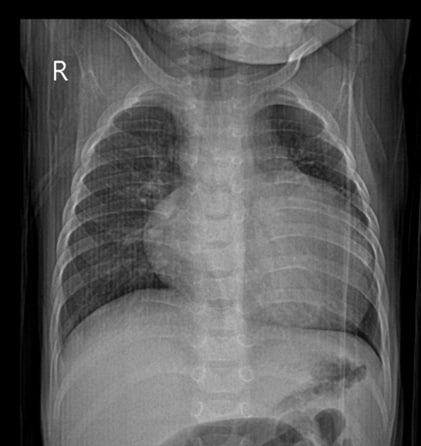

Для дальнейшего лечения и наблюдения пациент был переведен в ГБУЗ СК КДКБ г. Ставрополь отделение кардиологии и ревматологии, где в дальнейшем проводились лабораторно-инструментальные методы исследования, а также патогенетическая и симптоматическая терапия. Было выполнено рентгенографическое исследование органов грудной клетки, где выявлены признаки сгущения легочного рисунка в проекции S3 правого легкого; рентгенпризнаки резко выраженной кардиомегалии; тень сердца резко расширена в поперечнике, КТИ= 0,71 (рис. 1).

Рисунок 1 - Рентгенография органов грудной клетки на момент госпитализации в ГБУЗ СК КДКБ г. Ставрополь